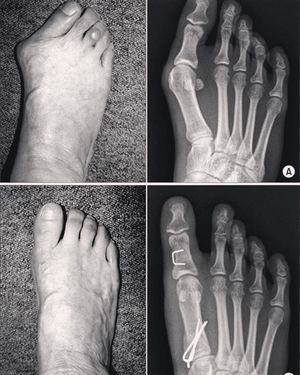

It is a deformity seen in the first metatarsal as it gets deviated medially with lateral rotation of the hallux. It is of higher incidence in females than males of a ratio of 2:1 to 4:1. About 70% of patients with Hallux Valgus have a positive family history. Treatment can be opertaive and non-operative. Non-operative treatment mainly focuses on wearing a special shoes, while operative treatment is by surgical correction. Figure(A, and B) shows the deformity before and after the surgery.